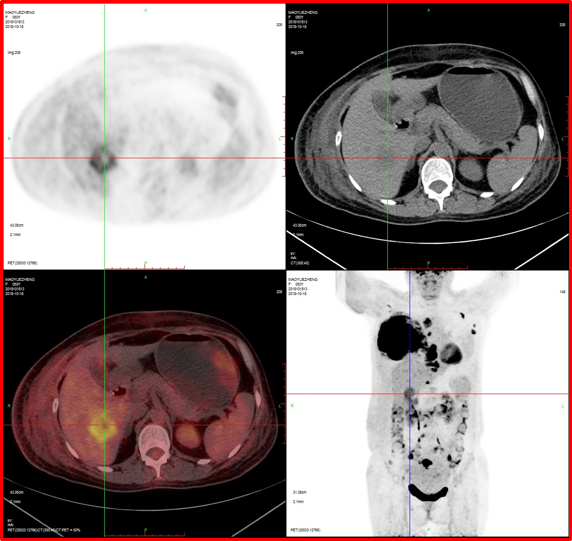

病例3:男性,72歲。結(jié)腸腺癌術(shù)后3年,右肺鱗癌術(shù)后1年隨訪。

4、肝脾多發(fā)轉(zhuǎn)移灶可能。